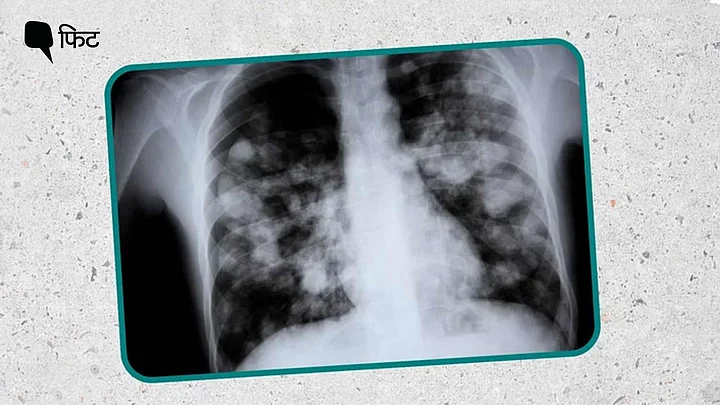

इस कंडीशन में फेफड़े में तरल पदार्थ की मौजूदगी की वजह से इमेजिंग के दौरान सफेद या अपारदर्शी धब्बे दिखाई देते हैं और इसीलिए इसे ‘व्हाइट लंग’ कहा जाता है.